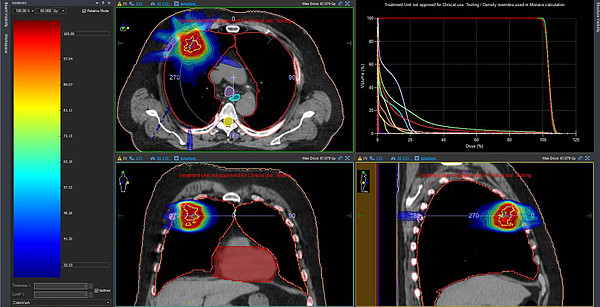

Этот вид лечения за вторую половину прошлого года прошли 7 человек. Это инновационный метод борьбы с онкологией. При его применении лучи ионизирующего излучения направляют прямо на опухоль, а травматизация здоровых тканей вокруг нее практически исключена.

Данный метод применяют, чтобы уничтожать раковые клетки в тех местах, куда трудно добраться при операции или если обычная лучевая хирургия может повредить жизненно важные органы.

Часто метод применяют для борьбы с опухолями и метастазами в головном мозге, легких или печени.